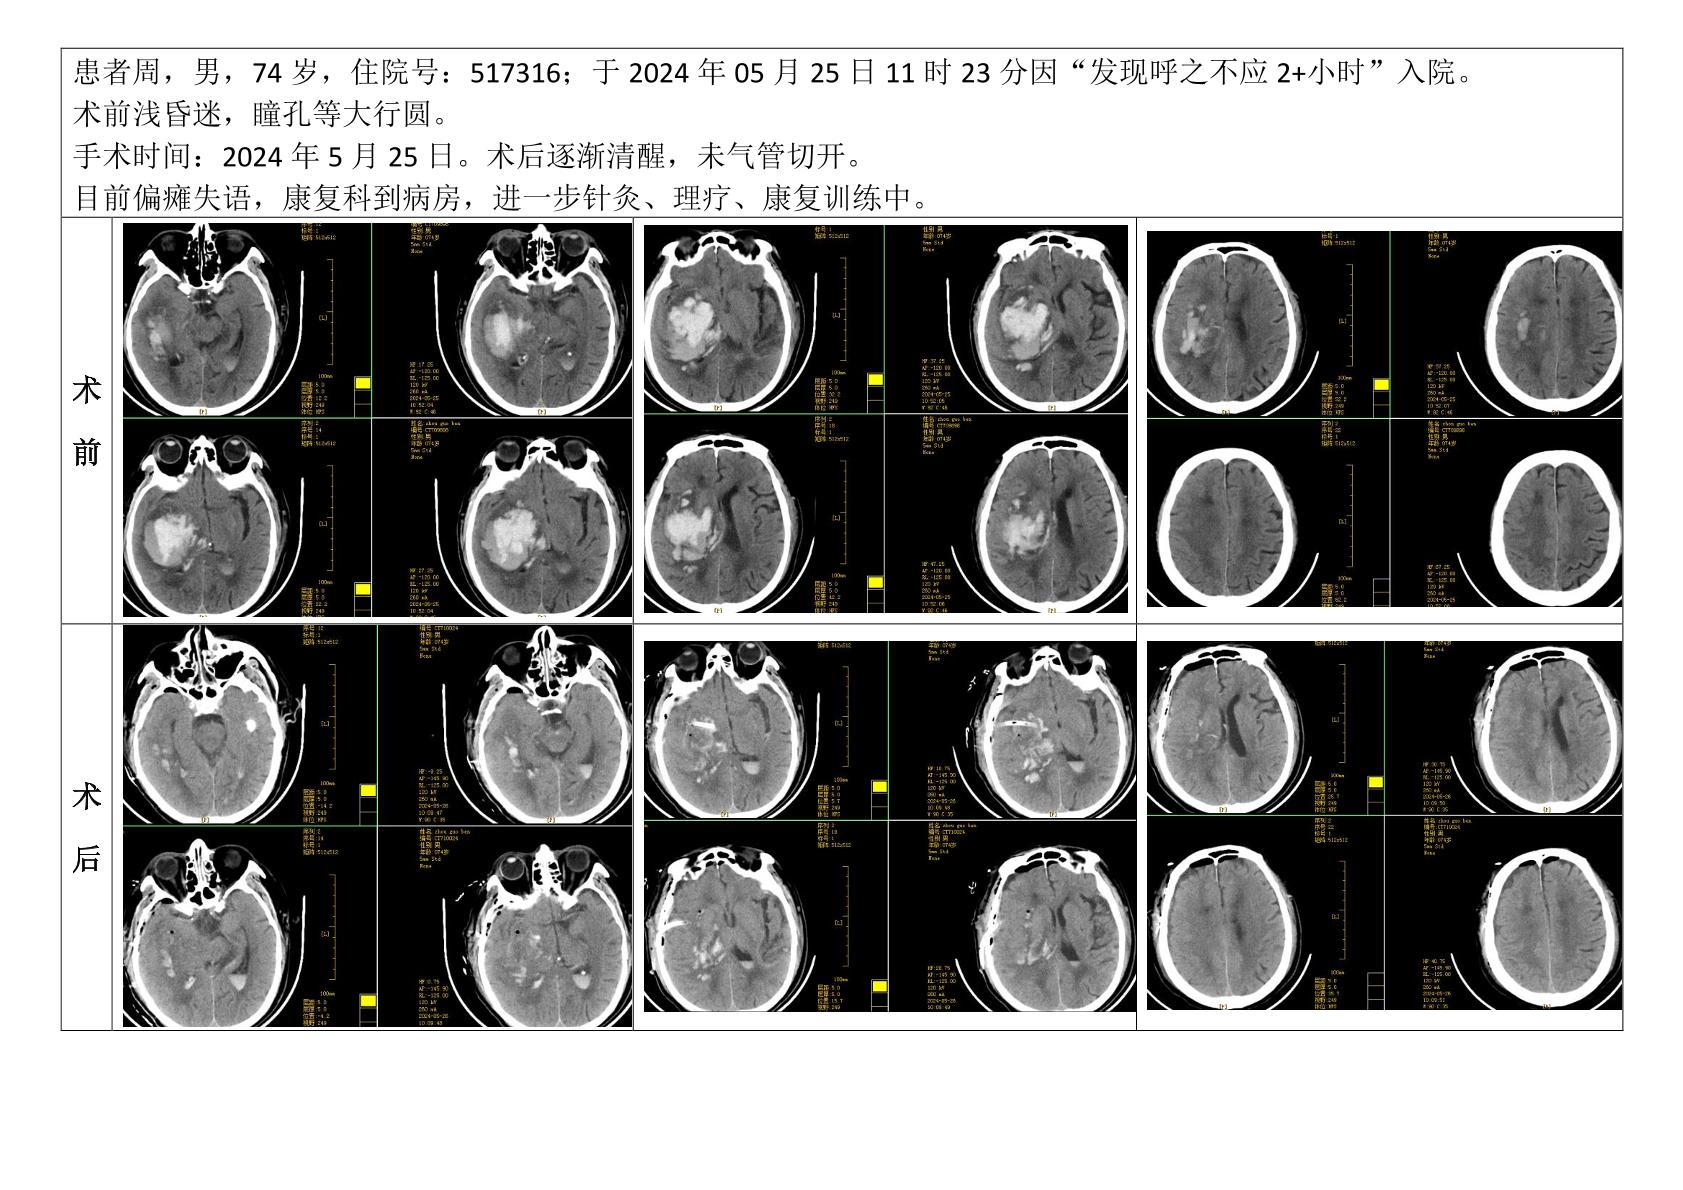

患者周某某,男,74岁,住院号:517316;于2024年05月25日11时23分因“发现呼之不应2+小时”入院。

术前CTA阴性.

术前浅昏迷,瞳孔等大行圆。

手术时间:2024年5月25日。

手术方式:翼点入路,小骨窗,经侧裂岛叶入路清除脑内血肿。

术后骨瓣复位

术后逐渐清醒,未气管切开。

目前偏瘫失语,康复科到病房,进一步针灸、理疗、康复训练中。

病例回顾:患者周,男,74岁,自发性基底节区脑出血,淀粉样变?